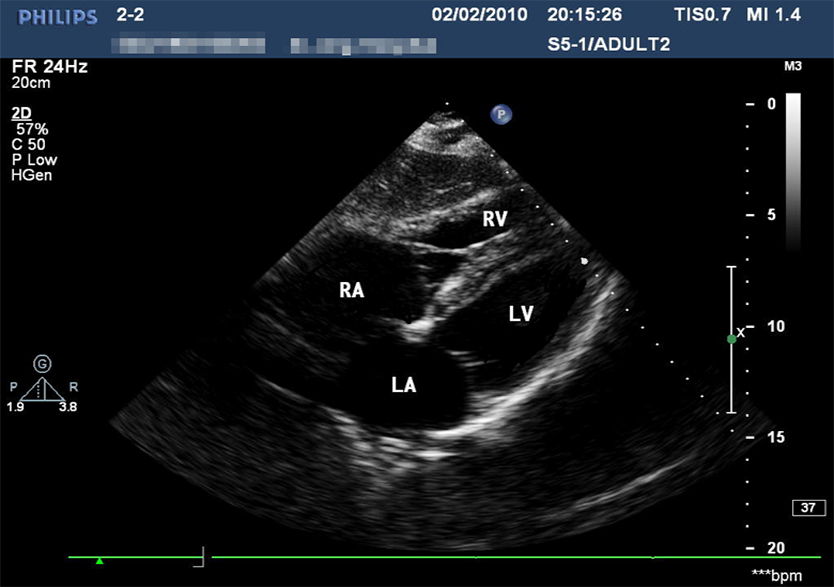

创伤超声重点评估平台2.0

产品型号 NO.TY4084

产品尺寸(mm) 987×444×269

让真实触手可及

TELLYES VIRTUALLY REAL